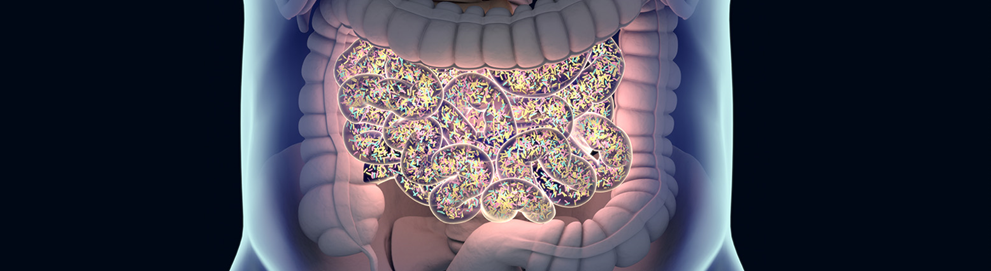

Our facilities, environment and collaborations/networks allow Oncodesign Services to work with preclinical and clinical samples (GLP/GcLP compliant environment in bioanalysis) and to manipulate live microorganisms (BSL2, BSL3 and GMO2 compliant laboratories).

Models & Readouts in microbiome

Oncodesign Services proposes tools suitable for mimicking healthy and pathological situations, studying interplay with immune system for screening purpose and proof of concept.

Oncodesign Services offers a broad range of technological approaches for culturing, detecting, identifying and localizing microorganisms (bacteria, yeasts, etc.) in simple or complex samples (fluids, tissues) coming from preclinical studies or clinical trials.